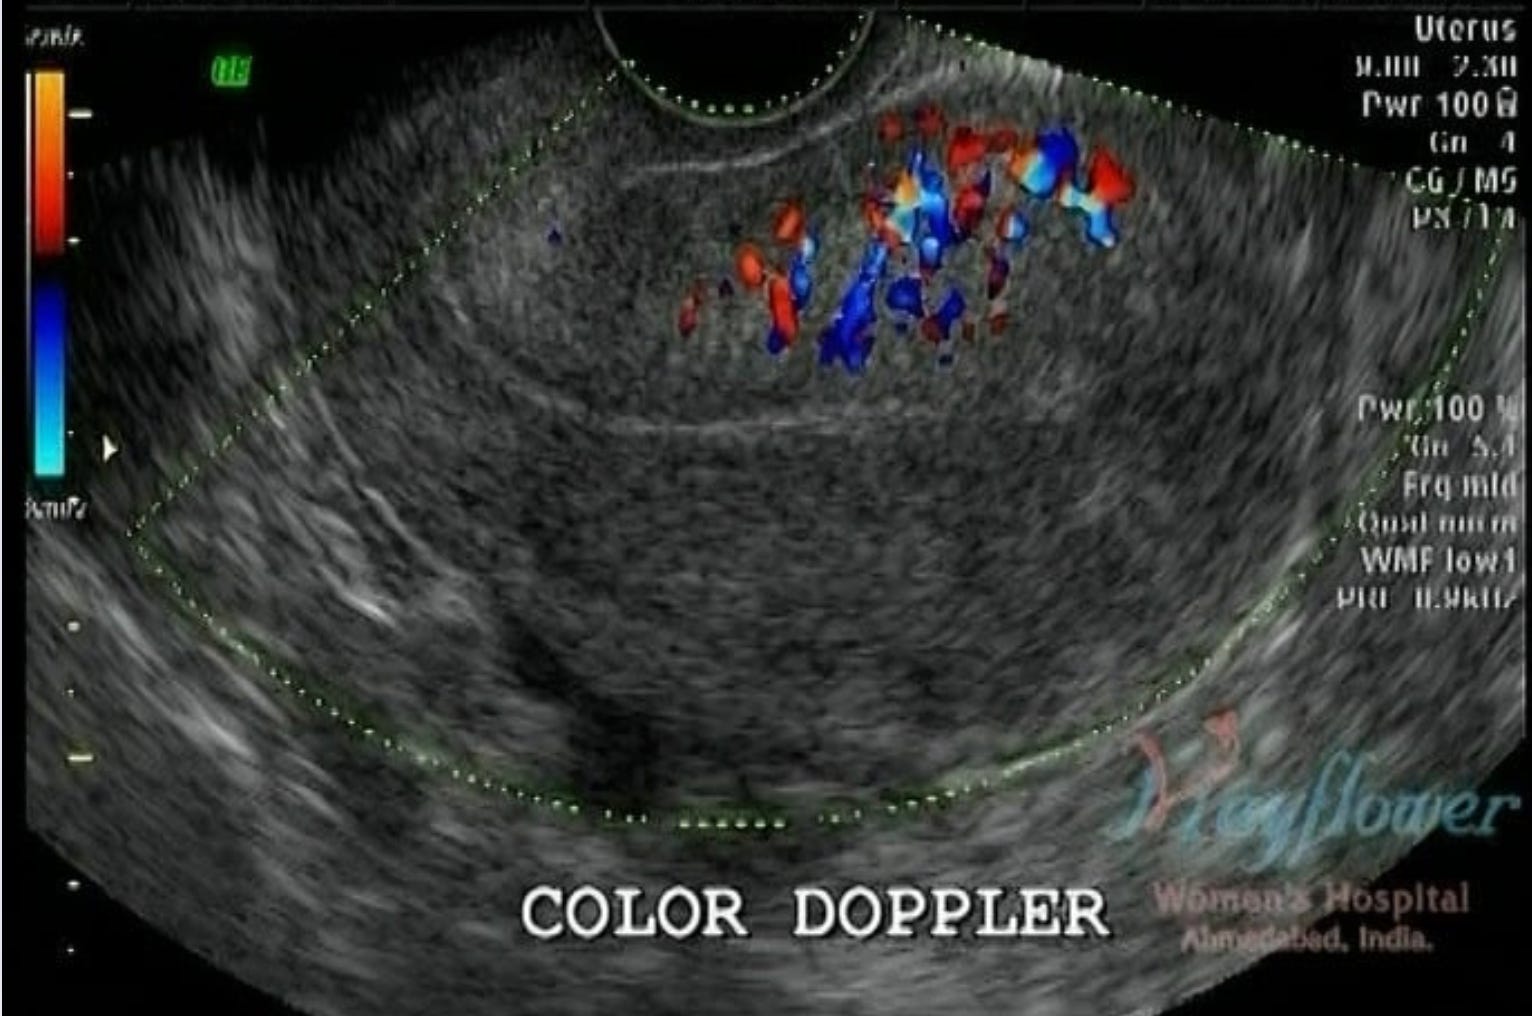

With an ectopic growth of endometrium-type tissue, we also see an increased vascularity in the region, observed through a Colour Doppler view. This vascularity also to a great extent helps us define the inner margins of the adenoma.

You can appreciate the core of the diseased region in the image above. Because of a lack of a clear margin of the disease in adenomyosis, this vascularity is a good approximation of that margin. In a different edition, we will talk about how this information aids surgical planning.